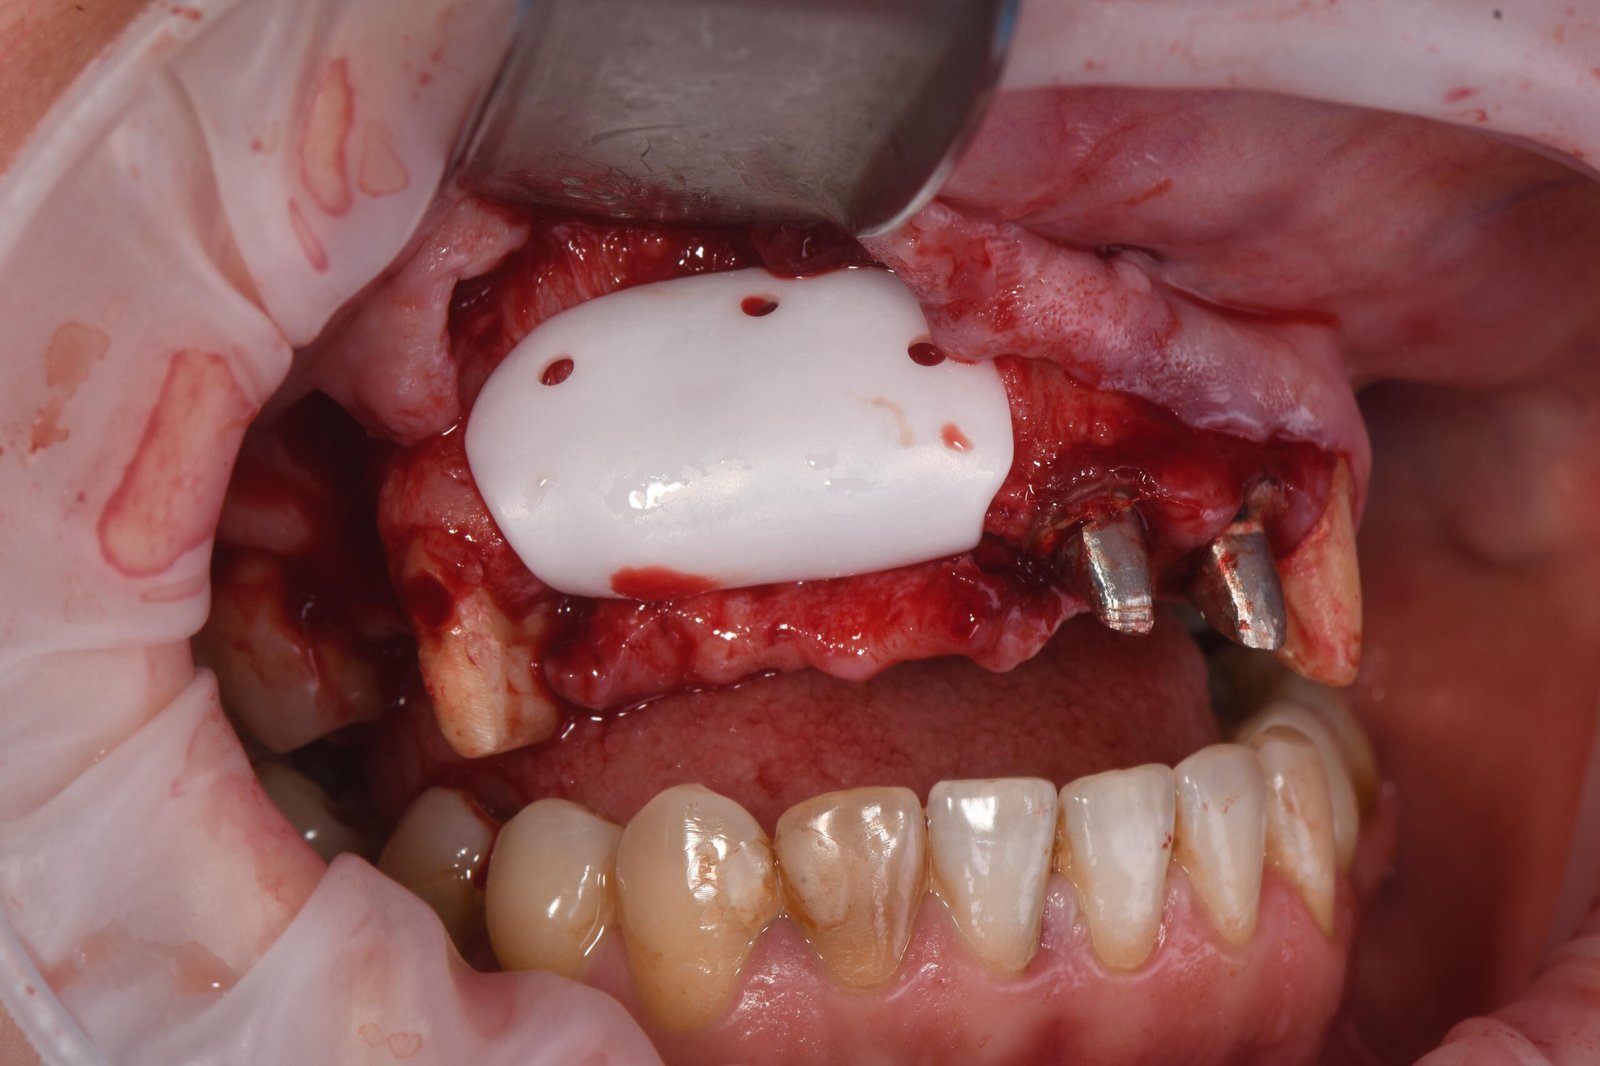

• Colocación de la barrera de zirconio.

• Fijación: secuencia correcta de atornillado.

• Control de estabilidad primaria.

• Cierre por planos y manejo de la tensión.

• Claves quirúrgicas para minimizar complicaciones.

• Suturas.